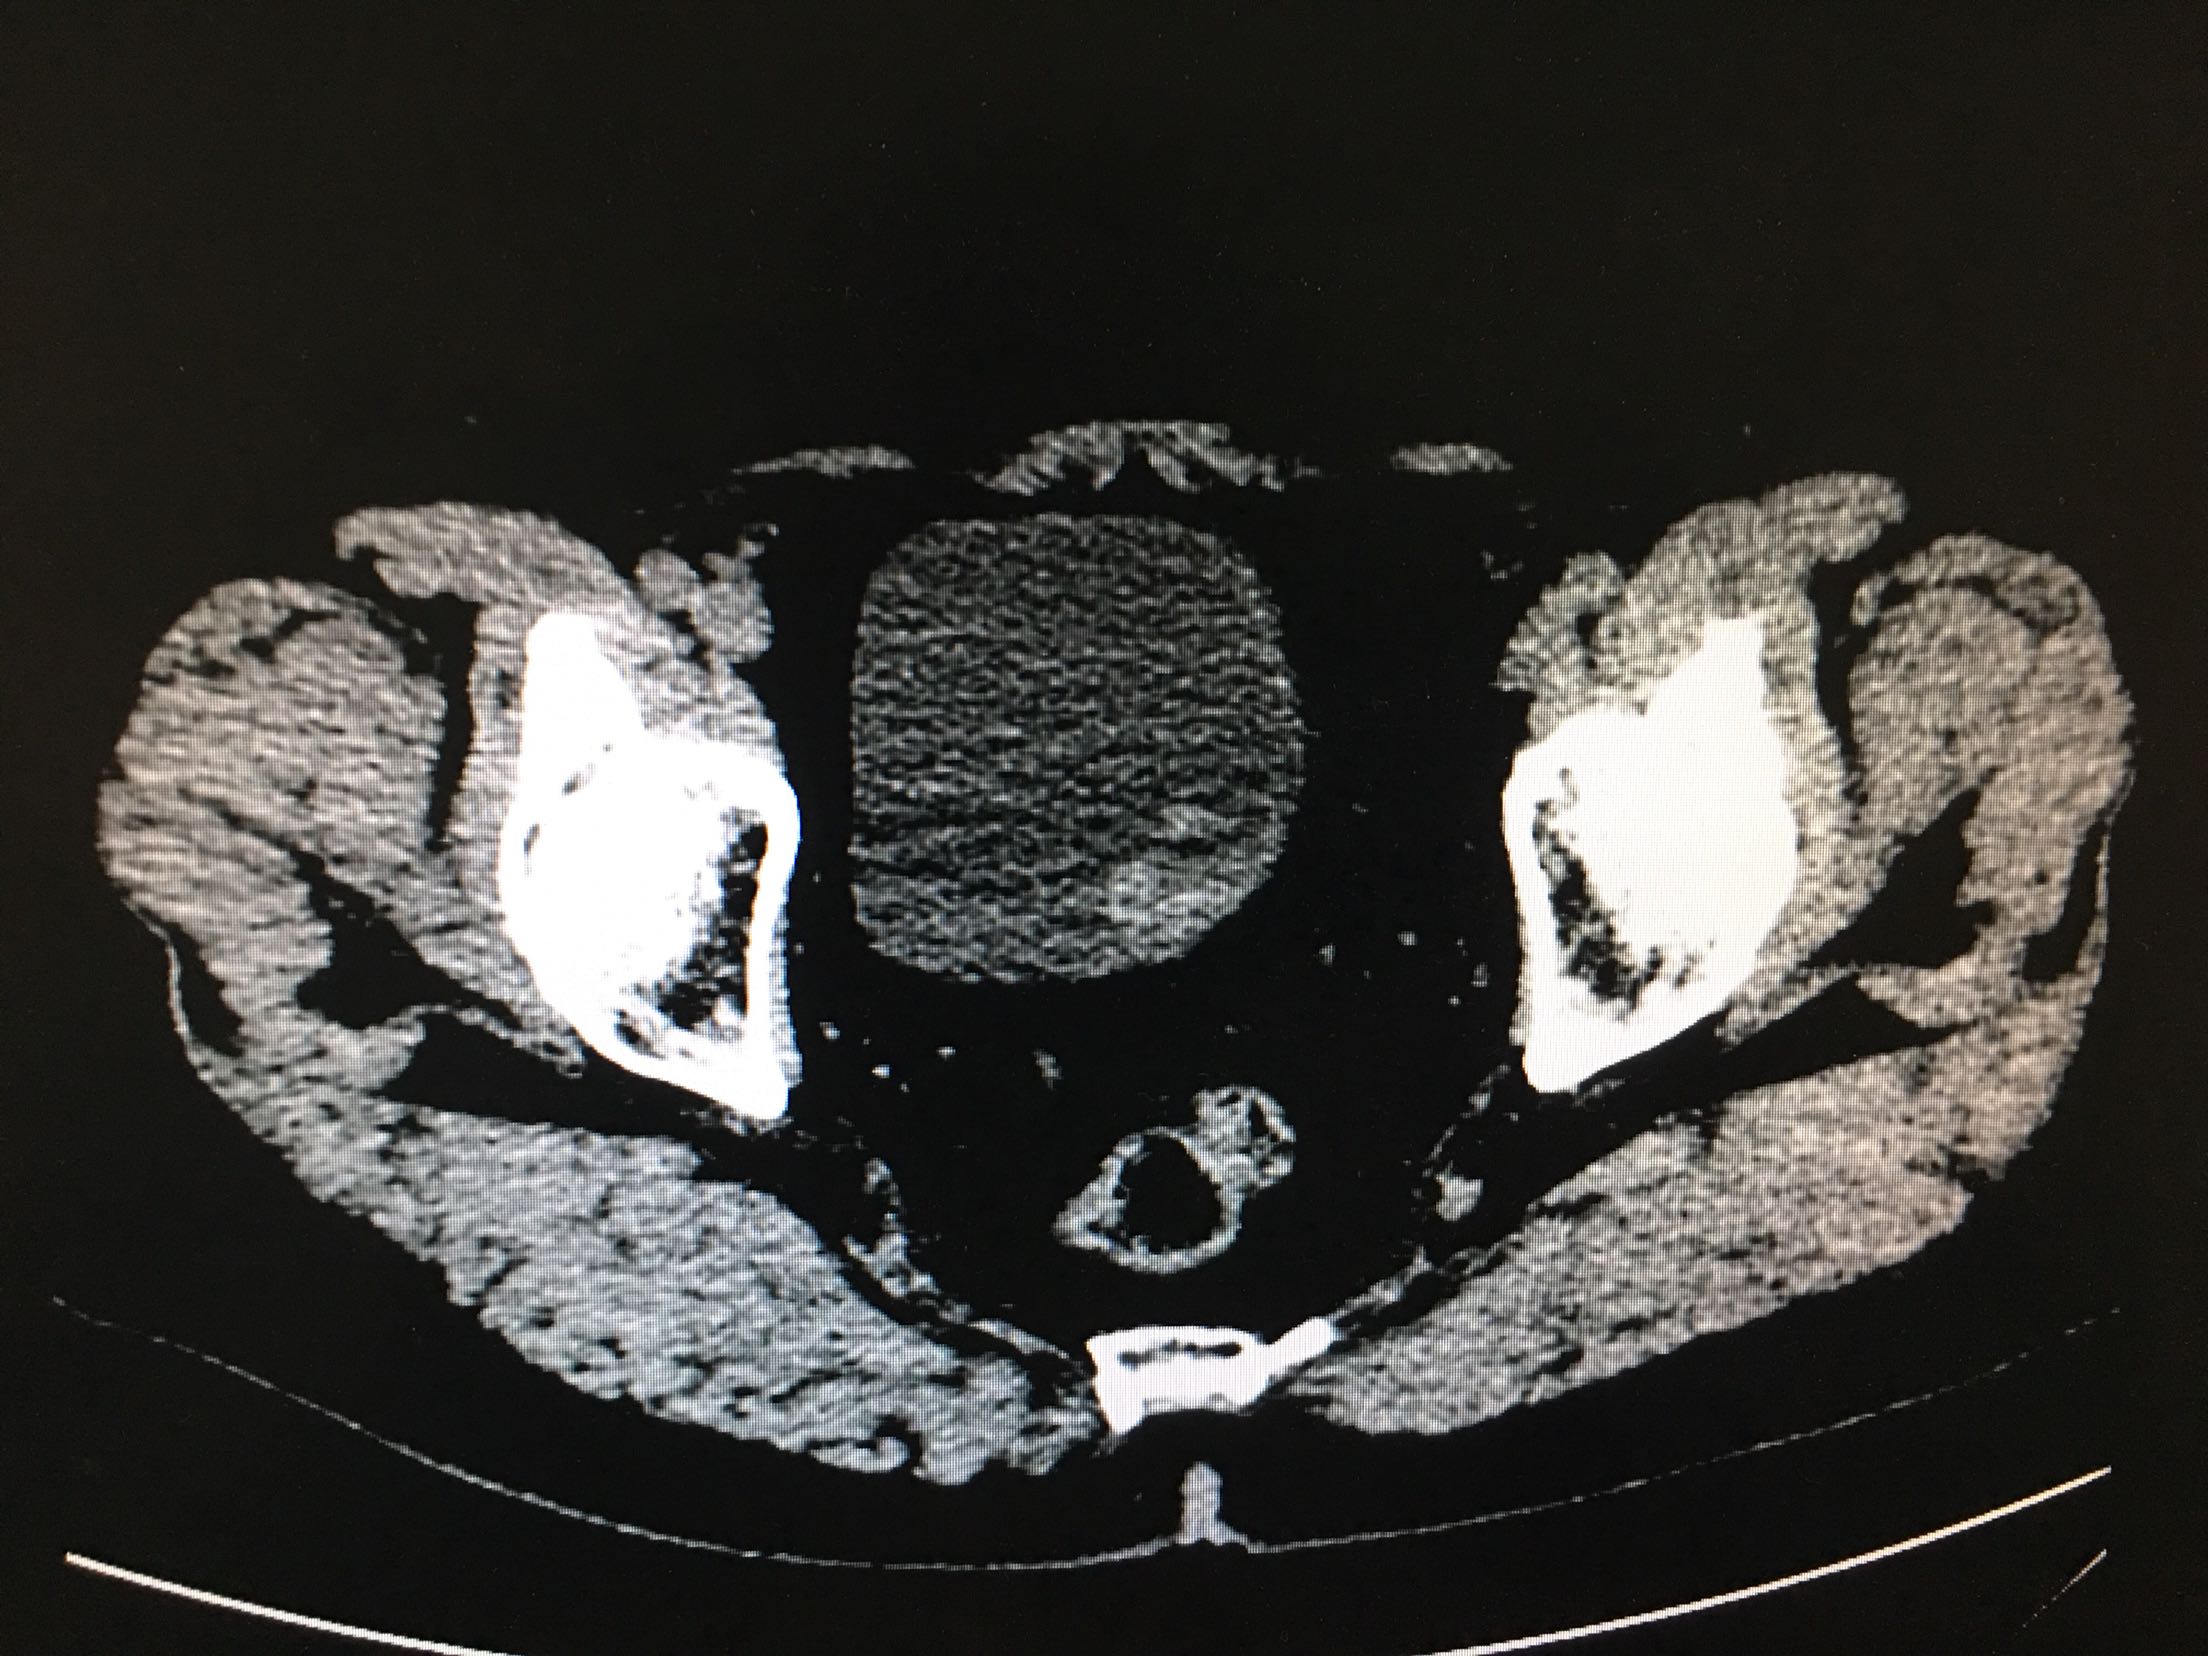

67岁男患者 2年前患者因为尿潴留检查发现前列腺癌,行经尿道前列腺癌电切改善排尿,术后给予内分泌治疗,5天前患者出现肉眼血尿,尿频、尿急、尿痛症状严重。患者为求进一步诊治来我院。患者发病以来精神状态差,体重减轻。

查体:双肾区无叩击痛,双输尿管走形区无压痛,耻骨上压痛,叩诊未见明确浊音。 辅助检查:ctu:膀胱占位性病变及直肠壁增厚,结合病史考虑前列腺癌伴膀胱及直肠受累。 psa:35ng/ml。